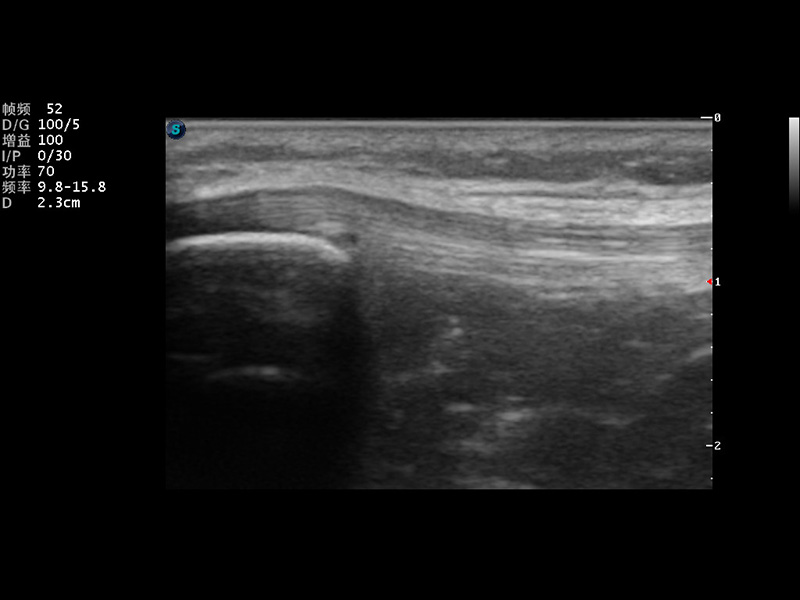

S9便携式彩色多普勒超声诊断仪是狗万官方网站研发的高端便携彩超设备,外观设计新颖、产品性能卓越。S9在便携超声领域采用了突破传统的触摸屏交互设计,并以先进的软件硬件技术和设计理念,为您带来清晰的图像质量、稳定的工作性能和便捷的操作体验。

VIS平台设计

μ-Scan微米成像

实时宽景成像